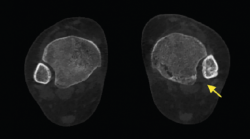

Patología sesamoidea

Uno de los aspectos importantes en la patología metatarsofalángica del primer radio y de los resultados postoperatorios de la cirugía del hallux valgus es la valoración del complejo sesamoideo en relación con el primer metatarsiano.

La deformidad estática y dinámica que comporta la desviación lateral de los sesamoideos es un aspecto destacable en toda la valoración de la deformidad del hallux valgus.

La cuantificación de la deformidad y la desviación del complejo, así como la comparativa contralateral, se pueden realizar con la TAC en carga(12).

- Valoración rotacional del primer radio y desplazamiento de los sesamoideos. Valoración de la deformidad y rotación del primer radio, así como el desplazamiento lateral de los sesamoideos (Figura 9).

Figura 9. Se aprecia un desplazamiento lateral de los sesamoideos en deformidad del hallux valgus.